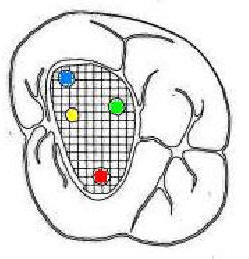

Segundo Molar superior

Presenta tres raíces: dos vestibulares y una palatina y a diferencia del primer molar superior estas no están tan separadas. Además, es frecuente encontrar fusionadas una de las raíces vestibulares con la palatina o ambas raíces vestibulares, formando una única raíz y conteniendo un solo conducto. Esta pieza dentaria puede presentar de tres a cuatro conductos y en raras oportunidades dos o uno.

Cuarto conducto en molares superiores (Color amarillo conducto mesio-palatino)